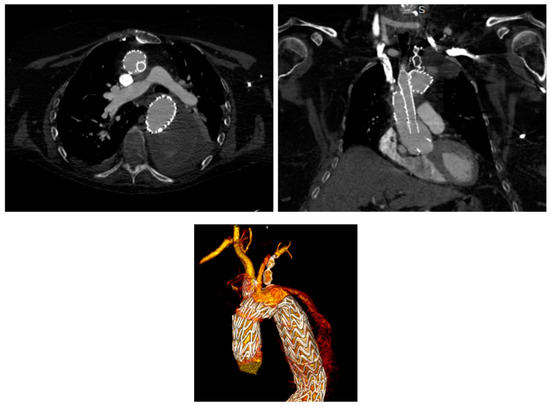

Total Endovascular Aortic Arch Repair Using In Situ Needle Triple Fenestration and Selective Cerebral Perfusion: Single-Center Results

Background: Advances in stent grafts and endovascular techniques have expanded the indications for thoracic endovascular aortic repair (TEVAR) to include arch lesions. In situ needle fenestration (ISNF) has emerged as a promising technique for revascularizing supra-aortic branches. The aim of this study is to evaluate the safety and efficacy of triple in situ needle fenestration during TEVAR for aortic arch pathologies in a single-center experience. Materials and Methods: A retrospective analysis was conducted on fifteen patients who underwent in situ triple fenestration TEVAR between June 2023 and March 2024. The median age of the patients was 51,33 years (±19.69) and twelve of the patients were male. All procedures were performed under general anesthesia in a hybrid operating room. Ethical approval was obtained from the institutional review board, and informed consent was received from all participants. Results: Primary technical success was achieved in all cases (15/15, 100%). The mean operation time was 197.33 min (range: 126–302). Two patients experienced a minor hematoma at the access site. Mortality was observed in one patient (6.66%) during the 30-day follow-up period. The total hospital stay averaged 7 ± 3.36 days. One patient had a transient ischemic attack, but there were no incidents of stroke or spinal cord ischemia. No procedure-related endoleak was observed during the intervention; however, eight patients required reintervention in the descending aorta. Conclusions: ISNF may be an effective and feasible method for revascularizing arch vessels, with low rates of early mortality and stroke when performed by experienced practitioners. However, larger multicenter studies with longer follow-up are needed to confirm the durability and long-term outcomes of this technique. Full article

Figure 1